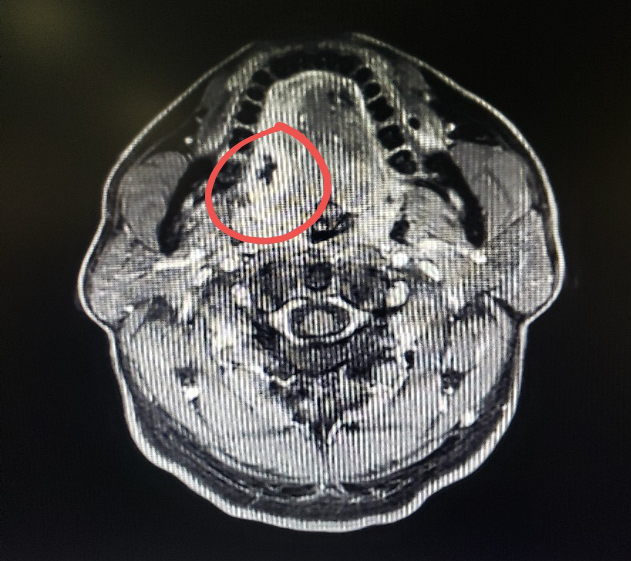

图一:病人的术前CT

图二:病人的术前MRI

图三:病人的术前MRI

图四:病人的术前MRI

那么这个异物包裹性脓肿里面到底是什么呢?我猜测要不是鸡骨,要不就是鱼刺,但鸡骨的话体积比较大,在CT上一般能看得出来,而且这么大的鸡骨插进舌头,病人的症状会非常明显,不会等到几个月后才来就诊。而鱼骨一般是很纤细的,在CT上是看不出来的,不过我们仔细看影像的话,还是可以在切面上发现小的阻射影的。